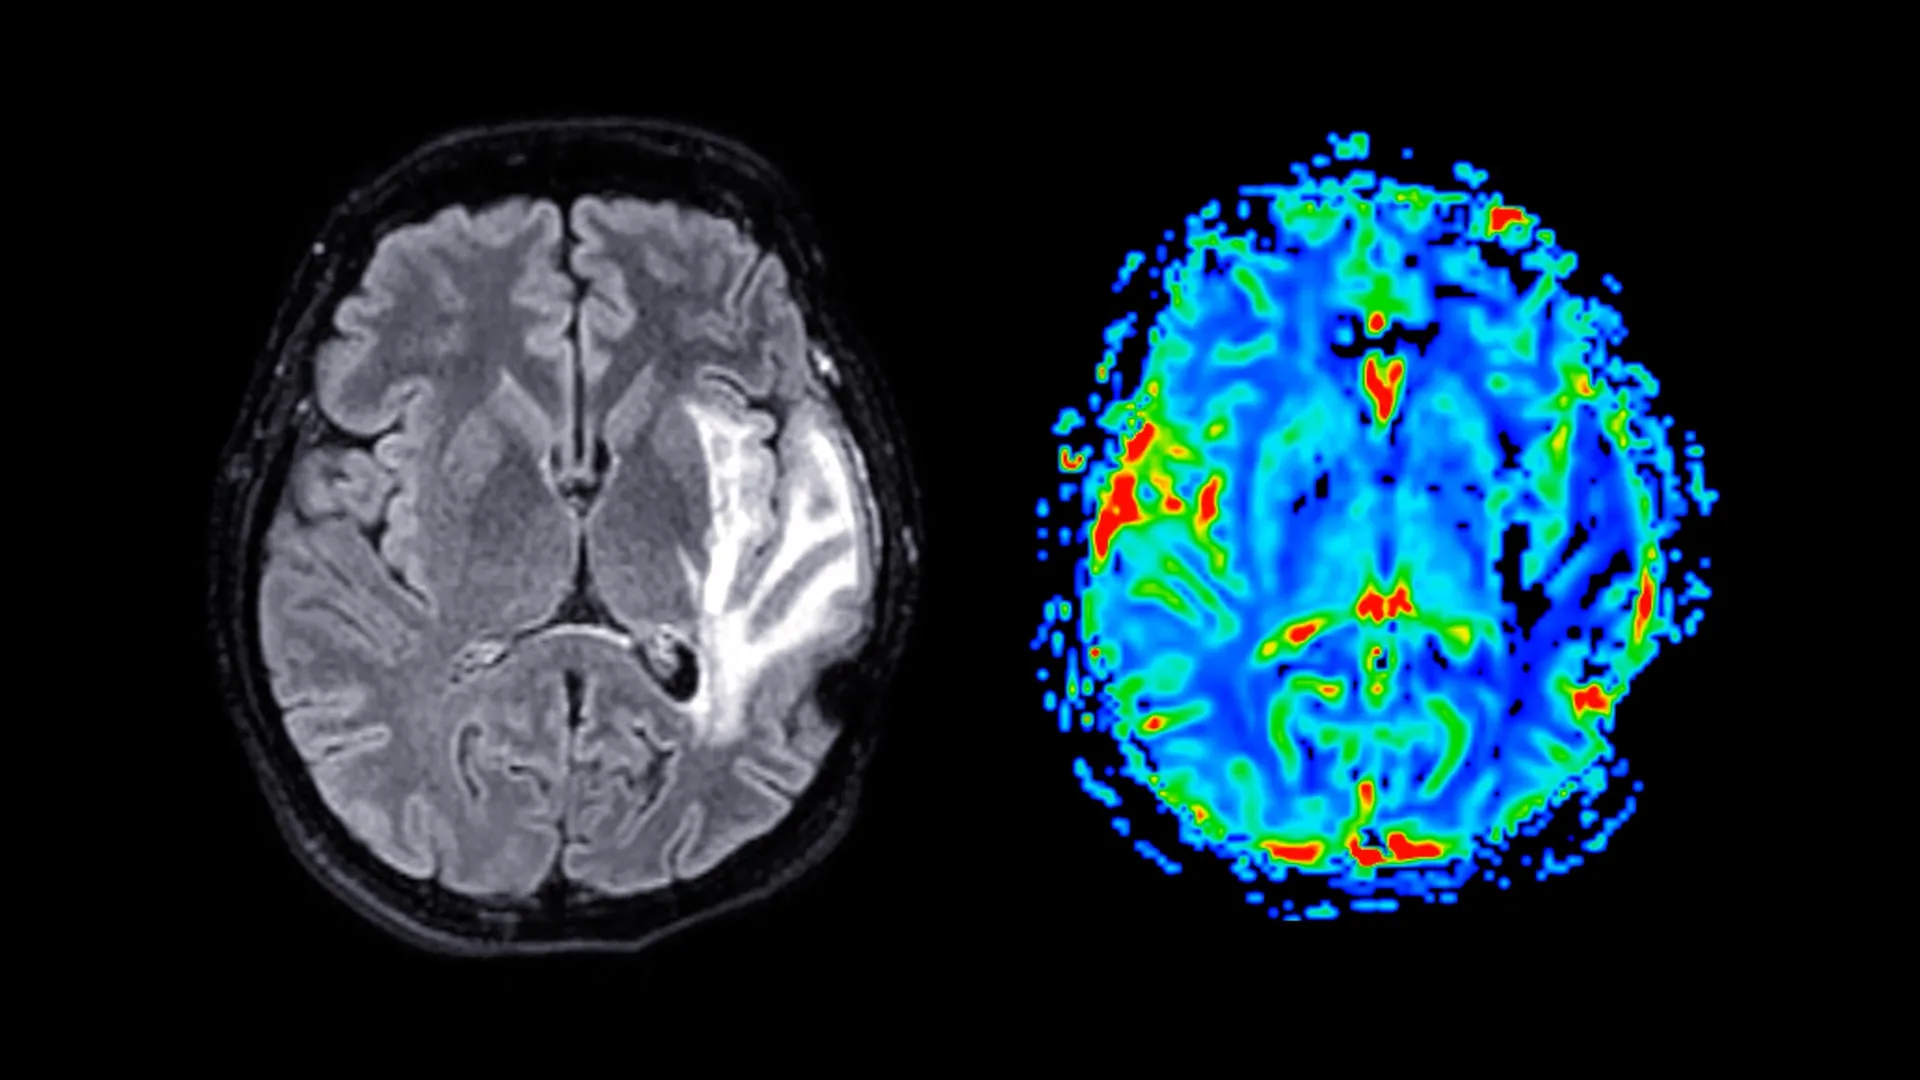

Dementia, a complex constellation of neurological disorders, represents a significant and escalating challenge to worldwide health systems, characterized by its progressive and currently incurable nature. Individuals affected by dementia experience a profound deterioration in cognitive faculties, encompassing memory recall, abstract thinking, and logical reasoning, often to the extent that their capacity for independent daily functioning is severely compromised. This umbrella term encompasses various conditions, with Alzheimer’s disease, vascular dementia, and mixed dementia being the most prevalent. At their core, these disorders involve the gradual destruction of neural pathways within the brain, leading to a compounding decline in mental acuity over time. As the pathology advances, individuals may encounter increasing difficulties with language comprehension and expression, problem-solving, and exhibit noticeable alterations in personality and behavior.